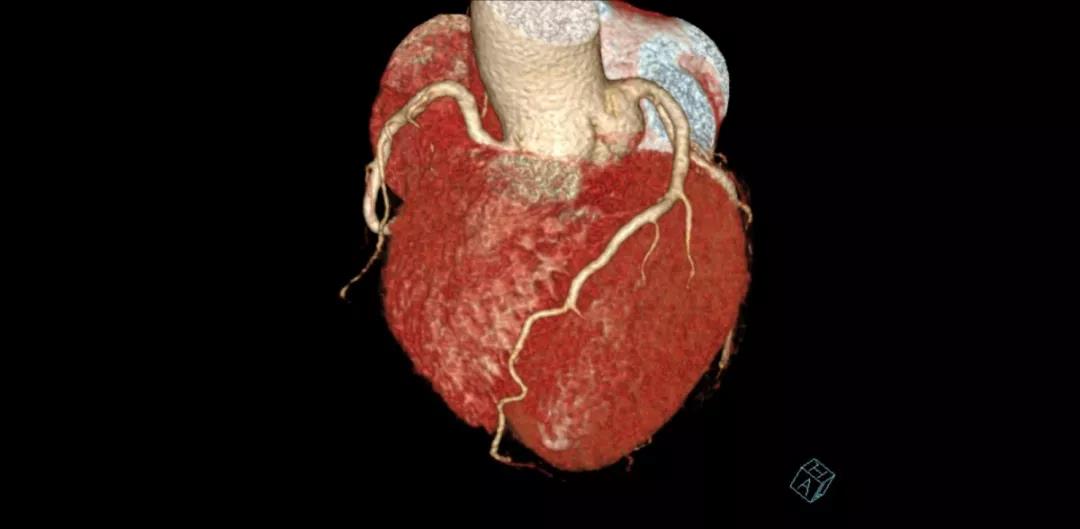

Somatom Definition Flash CT

雙源CT(雙源光子CT)

臨床應(yīng)用:

?具有成像速度快、輻射劑量低、時(shí)間分辨率高以及雙能量能譜成像的優(yōu)勢(shì)。

?尤其適合心臟及大血管成像、胸部低劑量篩查、痛風(fēng)石成像等檢查。

具體優(yōu)勢(shì):

?無需控制心率:極限狀態(tài)下心臟掃描僅需0.25秒。

?綠色準(zhǔn)確:雙源兩套128層數(shù)據(jù)采集系統(tǒng),提升了圖像質(zhì)量及診斷正確率;輻射劑量大幅度降低,只需小于1mSv的輻射劑量即可完成心臟掃描;

?雙能量成像技術(shù):具有定量及成分分析功能,可用于痛風(fēng)石檢測(cè),結(jié)石成分分析,骨髓顯像等;

?雙能祛金屬偽影技術(shù):減少金屬植入物對(duì)成像的干擾,使內(nèi)固定術(shù)后評(píng)估準(zhǔn)確。

案例圖

冠狀動(dòng)脈CTA